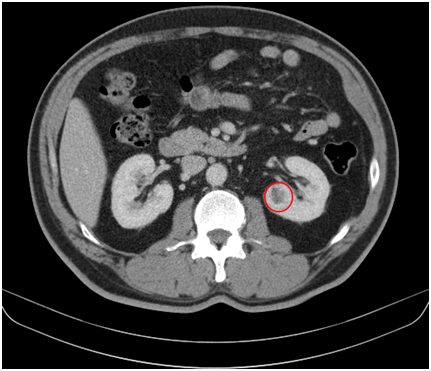

图一:肾脏增强ct提示左肾肿瘤,红色标记处即为肾肿瘤

图片尺寸431x371